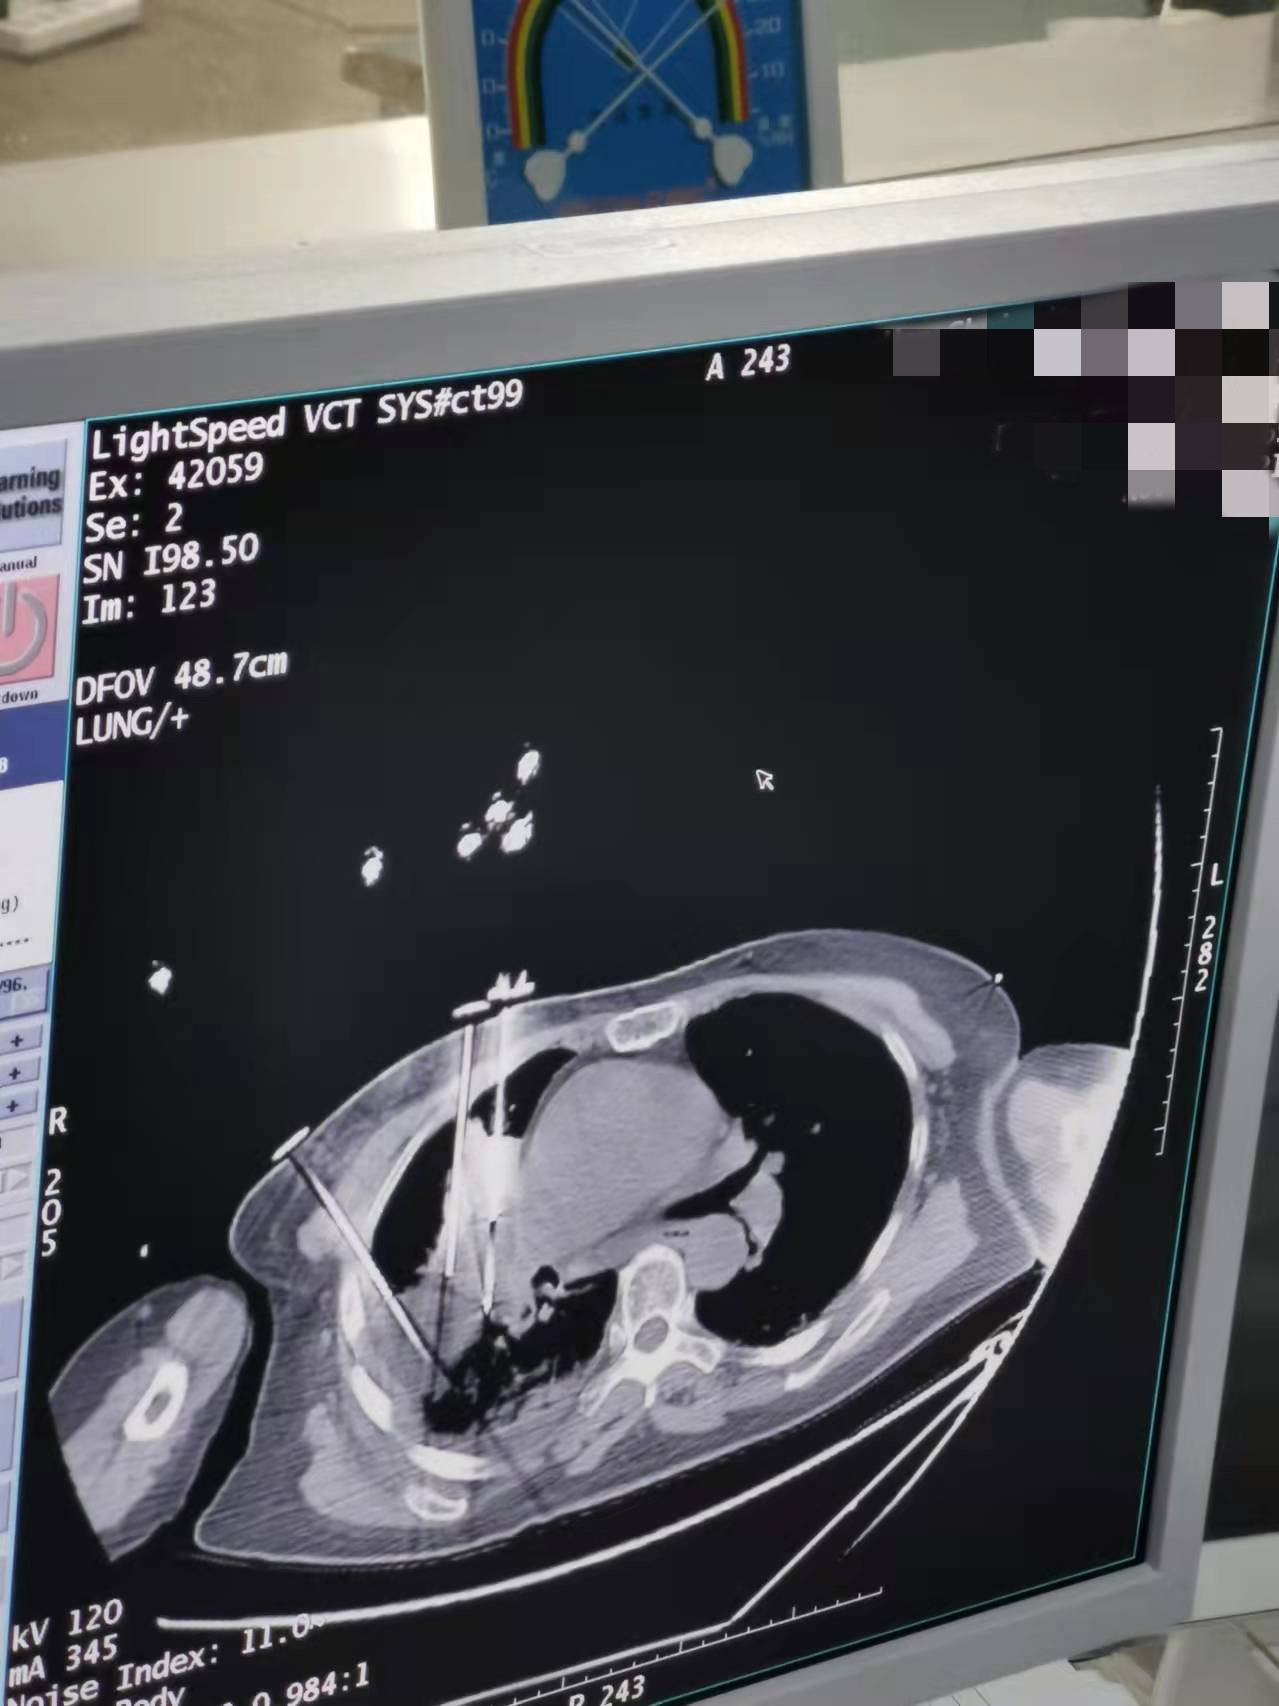

2021年11月份肺部氩氦刀手术

发布人:美国氩氦刀技术官方网站    发布时间:2021/11/26 14:02:23